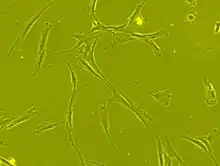

Mesenchymal stem cells (MSCs), a term first named (1991) by Arnold I. Caplan at Case Western Reserve University,[5] are characterized morphologically by a small cell body with a few cell processes that are long and thin. While the terms mesenchymal stem cell (MSC) and marrow stromal cell have been used interchangeably for many years, neither term is sufficiently descriptive:

Morphology

The cell body contains a large, round nucleus with a prominent nucleolus, which is surrounded by finely dispersed chromatin particles, giving the nucleus a clear appearance. The remainder of the cell body contains a small amount of Golgi apparatus, rough endoplasmic reticulum, mitochondria, and polyribosomes. The cells, which are long and thin, are widely dispersed, and the adjacent extracellular matrix is populated by a few reticular fibrils, but is devoid of the other types of collagen fibrils.[11][12] These distinctive morphological features of mesenchymal stem cells can be visualized label-free using live cell imaging.

The International Society for Cellular Therapy (ISCT) has proposed a set of standards to define MSCs. A cell can be classified as an MSC if it shows plastic adherent properties under normal culture conditions and has a fibroblast-like morphology. In fact, some argue that MSCs and fibroblasts are functionally identical.[13] The study in Science, "Multilineage Potential of Adult Mesenchymal Stem Cells," describe how MSCs can undergo osteogenic, adipogenic and chondrogenic differentiation ex vivo. As of November 2023, this paper has been cited over 29,000 times. The cultured MSCs also express on their surface CD73, CD90 and CD105, while lacking the expression of CD11b, CD14, CD19, CD34, CD45, CD79a and HLA-DR surface markers.[14]